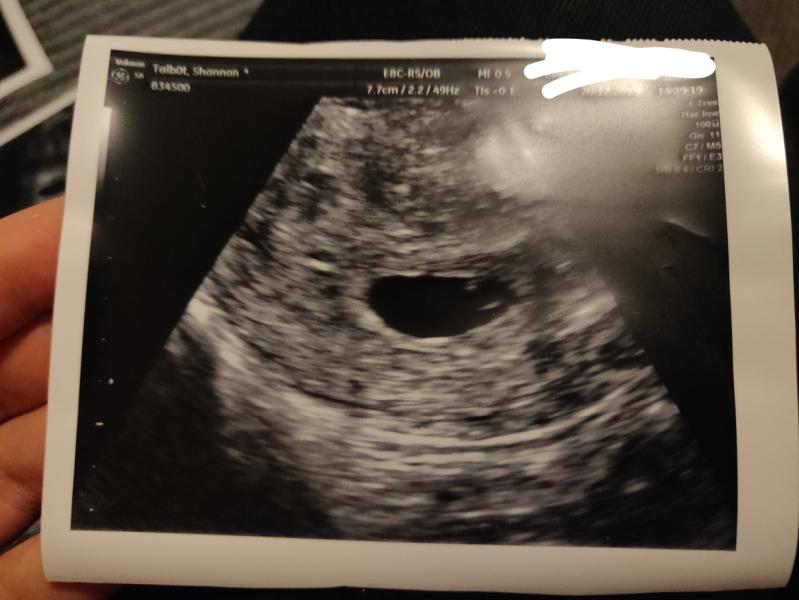

Had my 6 week scan, not quite 6 weeks yet so didn't get to see a heartbeat...

I think we may have prayed a little to hard for a baby. ITS TWINS!!! I'm in absolute shock 😳😍